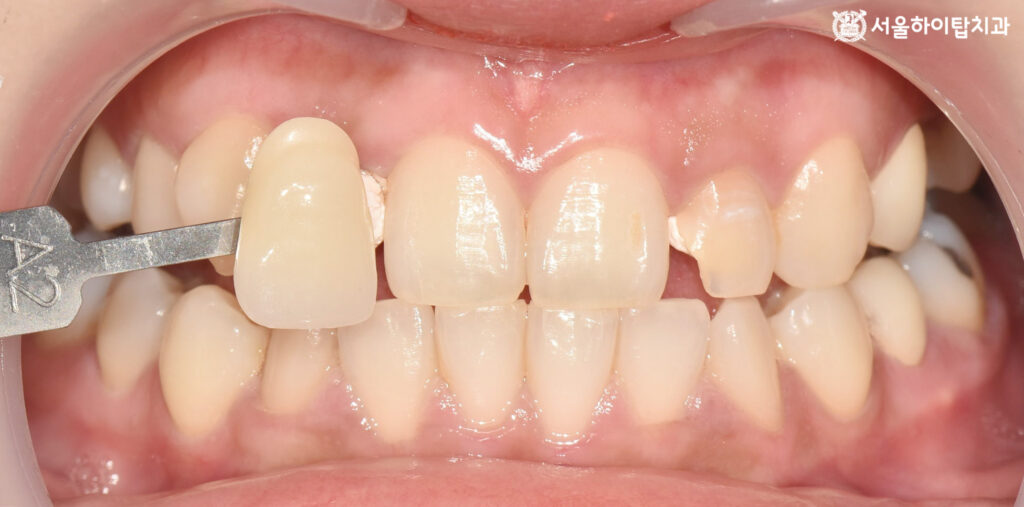

4. 쉐이드 테이킹(Shade taking)

마지막으로,

새로운 크라운으로 덮기 위해

훼손된 치아의 형태를 다듬는

prep 과정을 진행합니다.

형태가 정리되면,

쉐이드 테이킹(shade taking)을 통해

주변 치아와 어울리는 색을 선택합니다.

알맞은 색상이 선택되면

인상채득을 통해 맞춤형 보철을 제작하여

연결해 주면 모든 진료 과정은 종료됩니다.